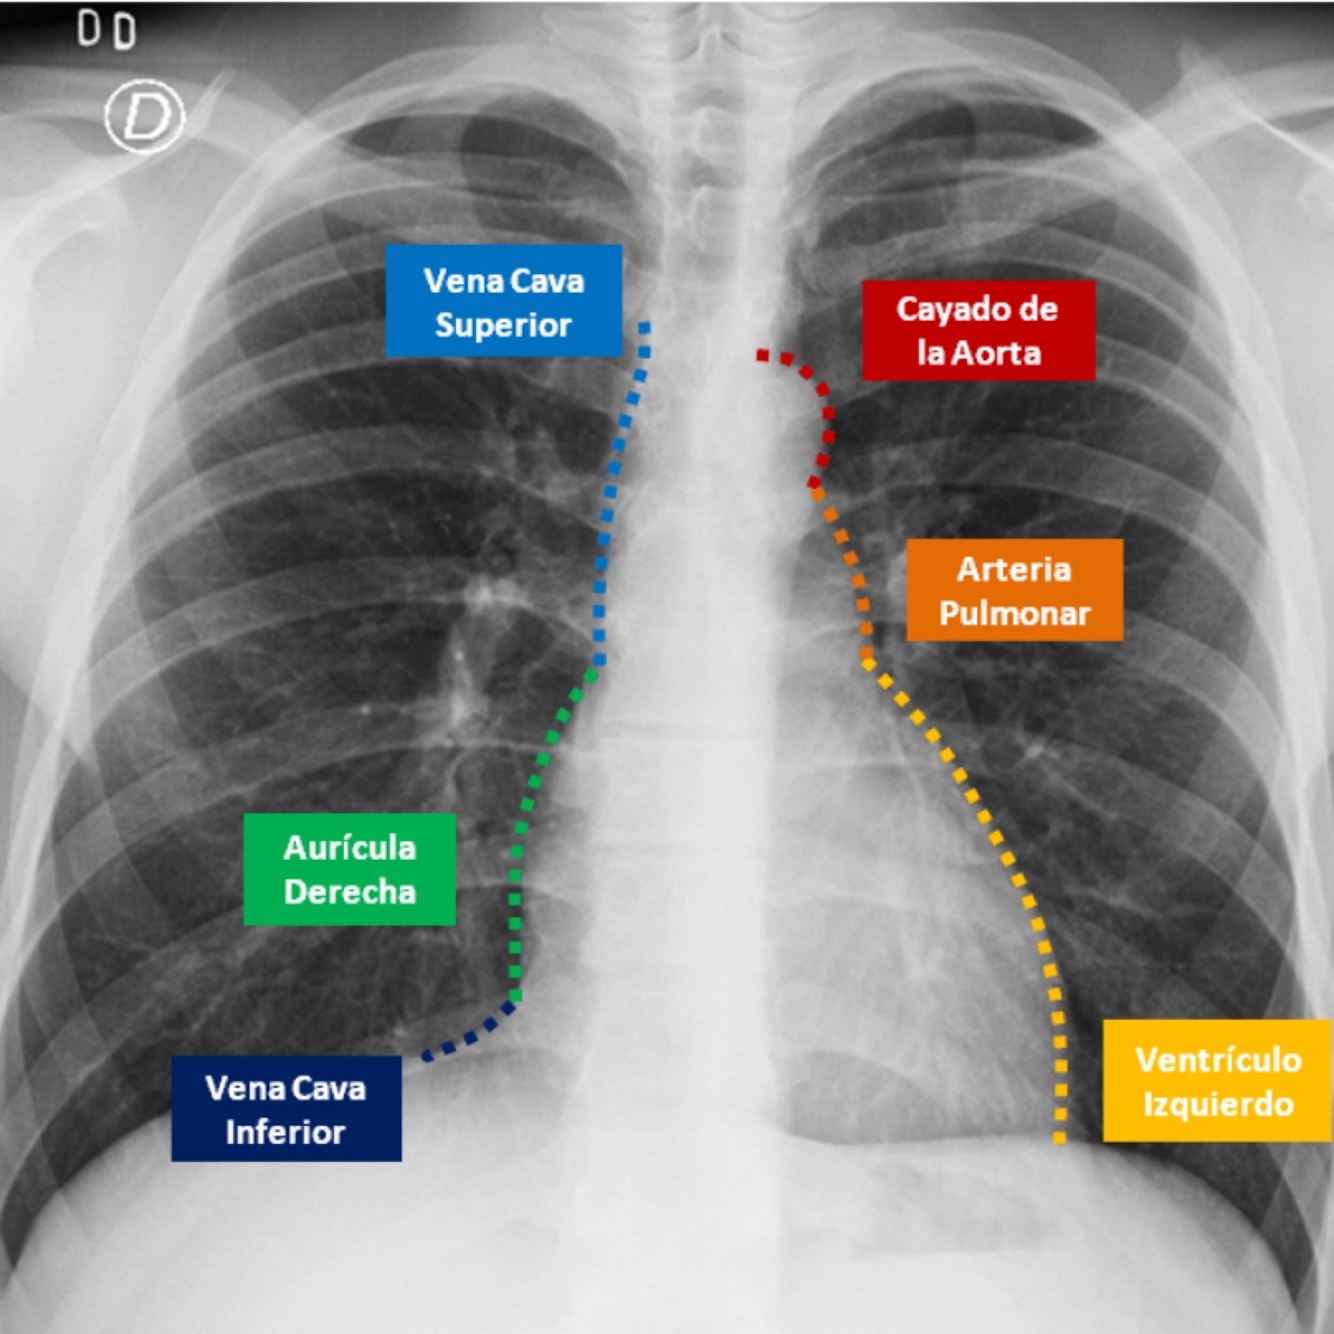

Q

Describe el perfil cardiaco